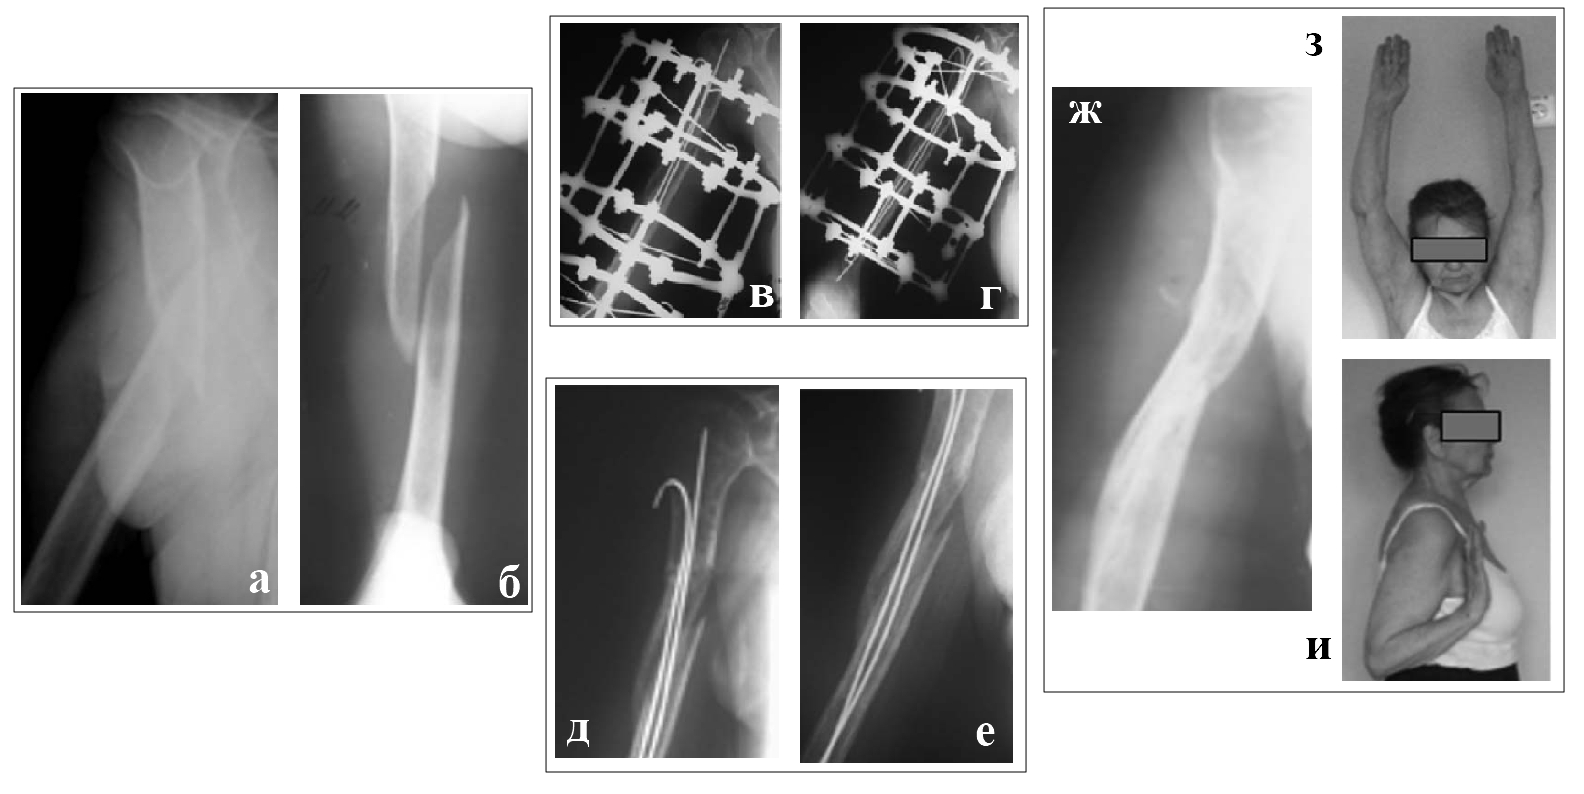

Первый клинический пример (рис. 2). Пациентка Ш., 77 лет. Диагноз: закрытый винтообразный перелом диафиза плечевой кости, остеопороз. Произведена закрытая репозиция отломков и остеосинтез плеча аппаратом Илизарова, интрамедуллярное армирование спицами с ГА покрытием. Лечение проходило в амбулаторных условиях. Период фиксации аппаратом Илизарова -1,5 месяца, а через 3 месяца после операции были удалены интрамедуллярные спицы: наступила консолидация и полностью восстановилась функция поврежденной конечности.

Рис. 2. Пациентка Ш.,77 лет. Рентгенограммы плеча:

а, б – до операции.

в, г - в процессе остеосинтеза аппаратом Илизарова;

д, е- через 6 недель после операции аппарат вмонтирован,

ж - через 3 мес. после операции.

(з, и) - фотография пациентки Ш. отражает полное функциональное восстановление после травмы